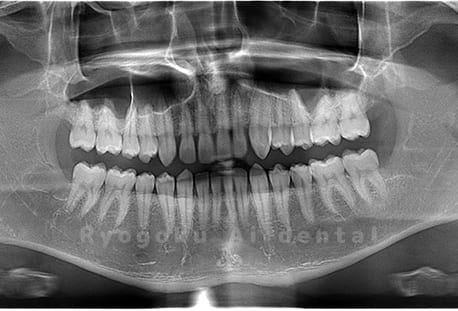

Case03

-

- 原因

- 上顎、下顎の親知らず

- 治療内容

- 上下4本の親知らずを抜歯したケースです。

<リスク・副作用>

手術後は痛み、腫れ、痺れなどの副作用が生じる場合があります。